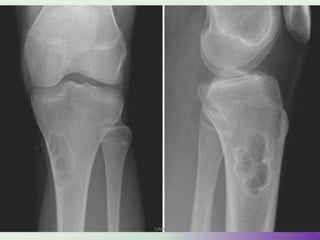

IMAGING

• X-rays

• epiphyseal

• well defined lytic lesions; either smooth or lobulated

margins with a thin sclerotic rim

• Internal calcifications can be seen in up to 40-60% of cases

• They range in size from 1-10cm, with most being 3-4cm at

diagnosis

• CT

• better delineation of the relationship to the growth plate

and articular surface

• Solid periosteal reaction (seen in up to 50% of cases) and

internal calcification (calcified matrix seen in ~ 1/2 of cases)

and cortical breach are also more easily appreciated.

• Endosteal scalloping may be seenUMY

• MRI

• Ideal for the evaluation of transphyseal or

transcortical extension.

• Demonstrating associated surrounding bone

marrow oedema.

• These lesions have signal typical of cartilage:

T1 - lesion itself is of low to intermediate signal

T2 / STIR - lesion is of intermediate to high signal

• Fluid-fluid levels may occasionally be seen .